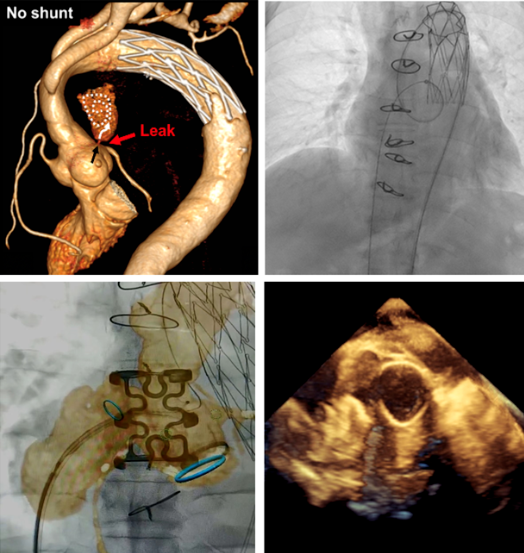

术前利用多种影像学方法评估吻合口漏,制定手术方案。

术中DSA、超声、图像融合等多种方法引导完成介入治疗。